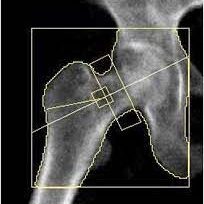

Unknown-1-3-3-204x247

Provides Axial Scan capability which includes hip and lumbar spine. The forearm is scanned in patients with bilateral hip replacement or lumbar surgery.